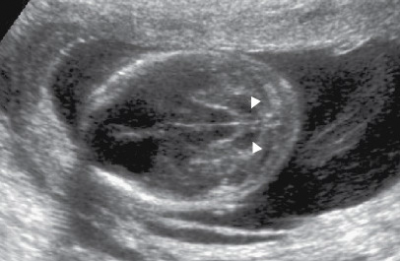

בבדיקת על-שמע בשליש השני להיריון נראה סימנים אופייניים למום בתעלה העצבית:

- סימן לימון (Lemon sign): שקיעה של העצמות המצחיות (Frontal). בתמונה רואים גם הגדלה של חדרי המוח (Ventriculomegaly);

- סימן בננה (Banana sign): בקיעה (Herniation) של המוחון והשטחה של הבְּרֵכָה הגדולה (Cisterna magna).

בכל המקרים נראה הגדלה של חדרי המוח וקוטר דו-קודקודי (BPD, Biparietal Diameter) קצר.